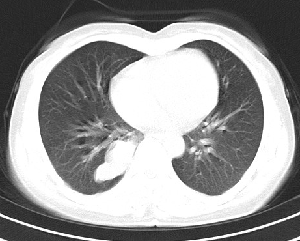

下叶后基底段近膈面见一椭圆形密度均匀增高的阴影,边界较清,其长轴指向内后方,考虑肺隔离症,建议增强扫描了解与主a联系!

右下肺隔离症有可能,另外可能是炎性假瘤

1\\没有什么病史吗,没有看到与腹主动脉有联系呀,肺隔离症不是太象

2\\如果没有明确临床体征,炎性假瘤到是可以考虑

右下肺隔离症考虑,不除外炎性假瘤,建议增强。